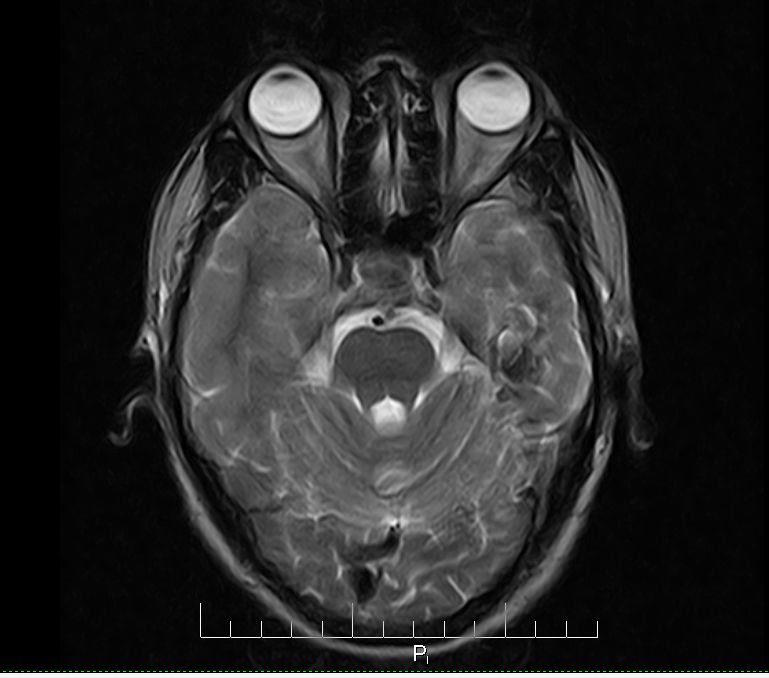

标题: MRI2379:30岁,男,癫痫10年,请各位看一下;CT示:左颞叶钙 [打印本页]

标题: MRI2379:30岁,男,癫痫10年,请各位看一下;CT示:左颞叶钙

左颞叶区见不规则点状混杂信号影

考虑血管畸形

支持2楼 左颞叶区见不规则点状混杂信号影,考虑动静脉畸形。

考虑左侧颞叶脑血管畸形(avm)。

考虑左侧颞叶脑血管畸形(avm)。----t1低等高混杂信号,t2等高信号周边较多流空血管影[冠状位明显],mra左侧大脑中动脉受压,远侧聚集.